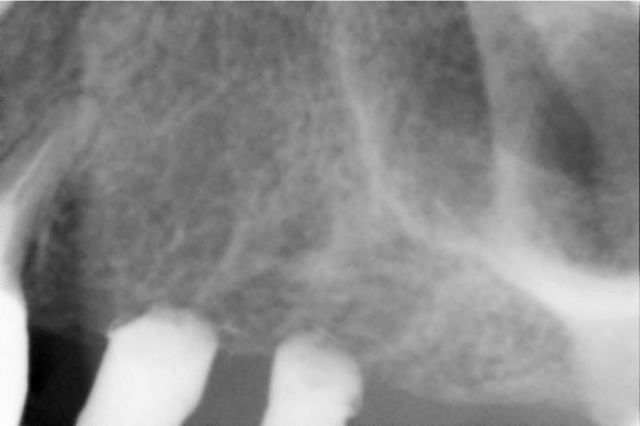

bon, je vous livre à chaud mes impressions positives et négatives:

ci joint 6 photos avant pendant et après,

je n'ai donc pas aplani comme conseillé,

j'ai passé le forêt pilote puis les ostéotomes 2.7 et 3.2,

le cliché de contrôle avant pose de l'implant montre bien le dôme du matériau de comblement, jusque là tout allait bien et je pensais que le plus dur était fait,

c'est après que j'ai été ennuyé:

j'ai commencé à visser à la main le WP de 5 mm

et j'ai rencontré une résistance quand il était à ras de la corticale V alors que du côté palatin j'avais une déhiscence de 2 mm ( normal je n'avais pas aplani)

j'ai eu l'impression qu'il perdait en stabilité et tournait sur lui même, curieux pour un os tendre?

la situation ne me plaisait pas et je l'ai dévissé, puis

j'ai élargi un peu au counterbore, et j'ai revissé,

aucune amélioration donc le problème était soit à l'apex de l'implant( perforation trop étroite pour le passage d'un implant cylindrique), ou alors le long des parois, auquel cas j'aurais dû passer un ostéotome de 3.7, ou même 4.2 ce qui me paraissait un peu trop pour un WP sur un os peu dense,

j'ai quand même réussi en changeant un peu l'inclinaison à le bloquer manuellement à 40 Ncm et sans déhiscence

qu'est-ce qui a pu résister au vissage de l'implant:

1- un os trop dense donc dernier ostéotome trop étroit?

2- un orifice de perforation de la corticale sinusienne trop étroit de 3.2 mm pour un implant de 5 mm non conique ?

3- autre chose que je n'ai pas vu ?

en tout cas, sur les clichés, le beau dôme que l'on voit avant implantation a disparu après pose de l'implant; où est le matériau?

a mon avis, c'est l'explication N°2.